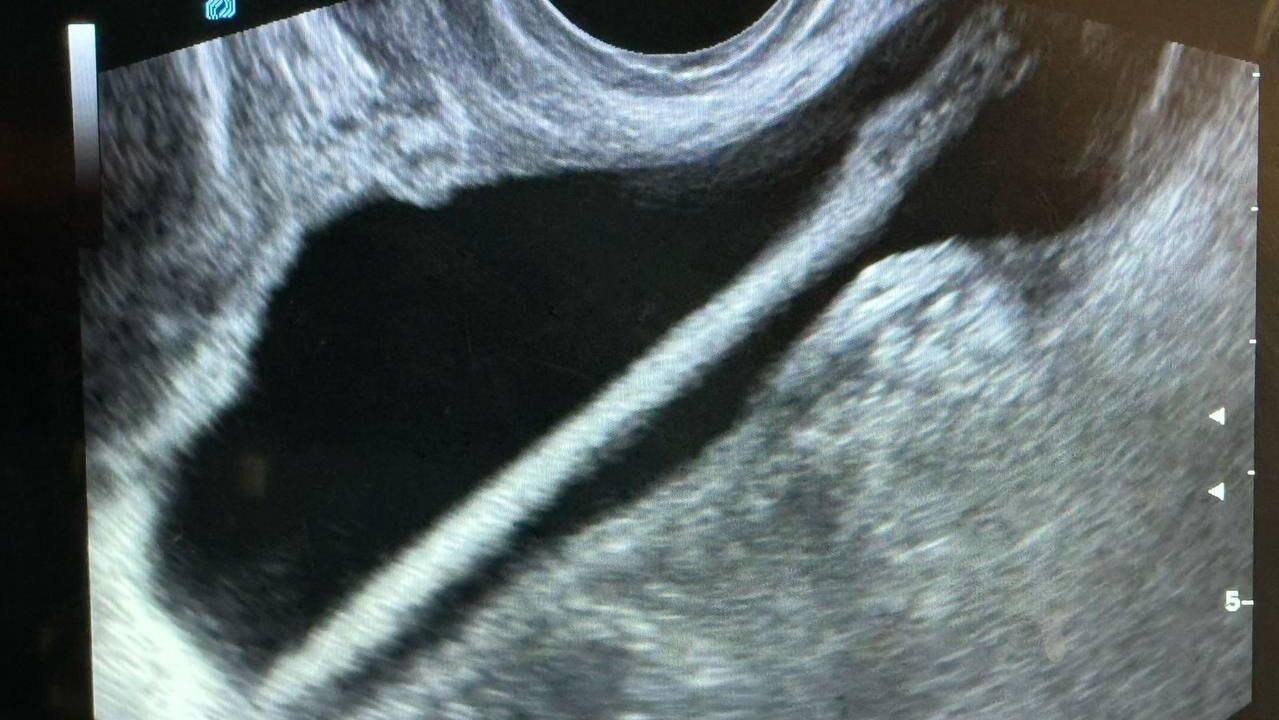

Врачи Красногорской больницы успешно удалили из мочевого пузыря 46-летней женщины косметический карандаш. Пациентка уже выписана, сообщили в Министерстве здравоохранения Московской области.

По информации ведомства, в приемное отделение больницы обратилась женщина, которая призналась, что самостоятельно ввела карандаш в мочеиспускательный канал. В результате инородное тело оказалось в мочевом пузыре, и ей потребовалась срочная медицинская помощь. Пациентку госпитализировали в урологическое отделение.

«Сначала женщине провели ультразвуковое исследование, после чего врачи выполнили операцию. С помощью эндоскопа инородное тело было удалено из мочевыделительного тракта. Операция прошла успешно, без осложнений», — сообщил заведующий урологическим отделением Красногорской больницы Пётр Сысоев.